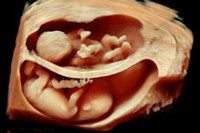

懷孕三個(gè)月胎兒長(zhǎng)成什么樣子呢?想必這是準(zhǔn)媽媽們想要迫徹知道的答案吧。自從準(zhǔn)媽媽成功受孕以來(lái),胎兒寶寶在肚子里靜靜的呆著,先是給準(zhǔn)媽媽們帶來(lái)一些妊娠不適的反應(yīng),...